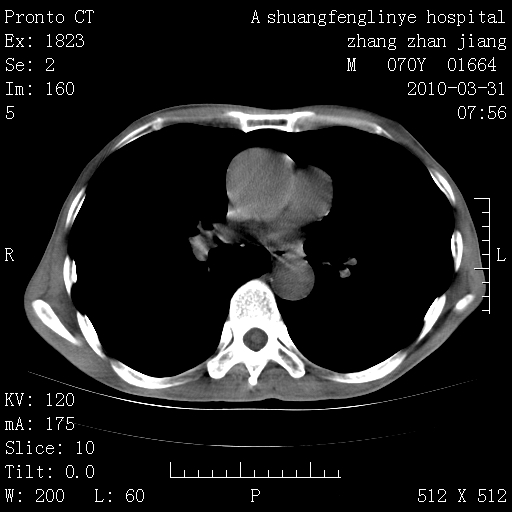

双上肺继发型tb并左上空洞形成,主动脉冠脉钙化。

1)两肺上叶继发性肺结核并左肺上叶空洞形成。2)冠状动脉及主动脉钙化。

支持,不过左肺中叶那个像陈旧病变的结节要不要单报一下,在图上没看到钙化单报一下放心啊